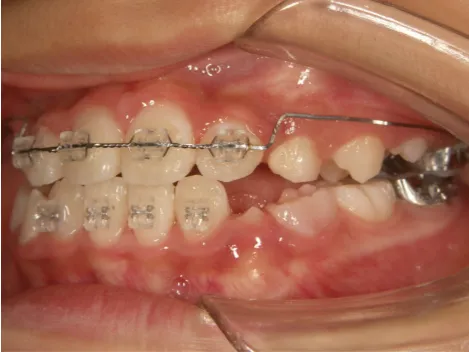

治療中⑧高1:15y11m 抜歯治療中

治療中⑨高2:17y1m 抜歯治療中